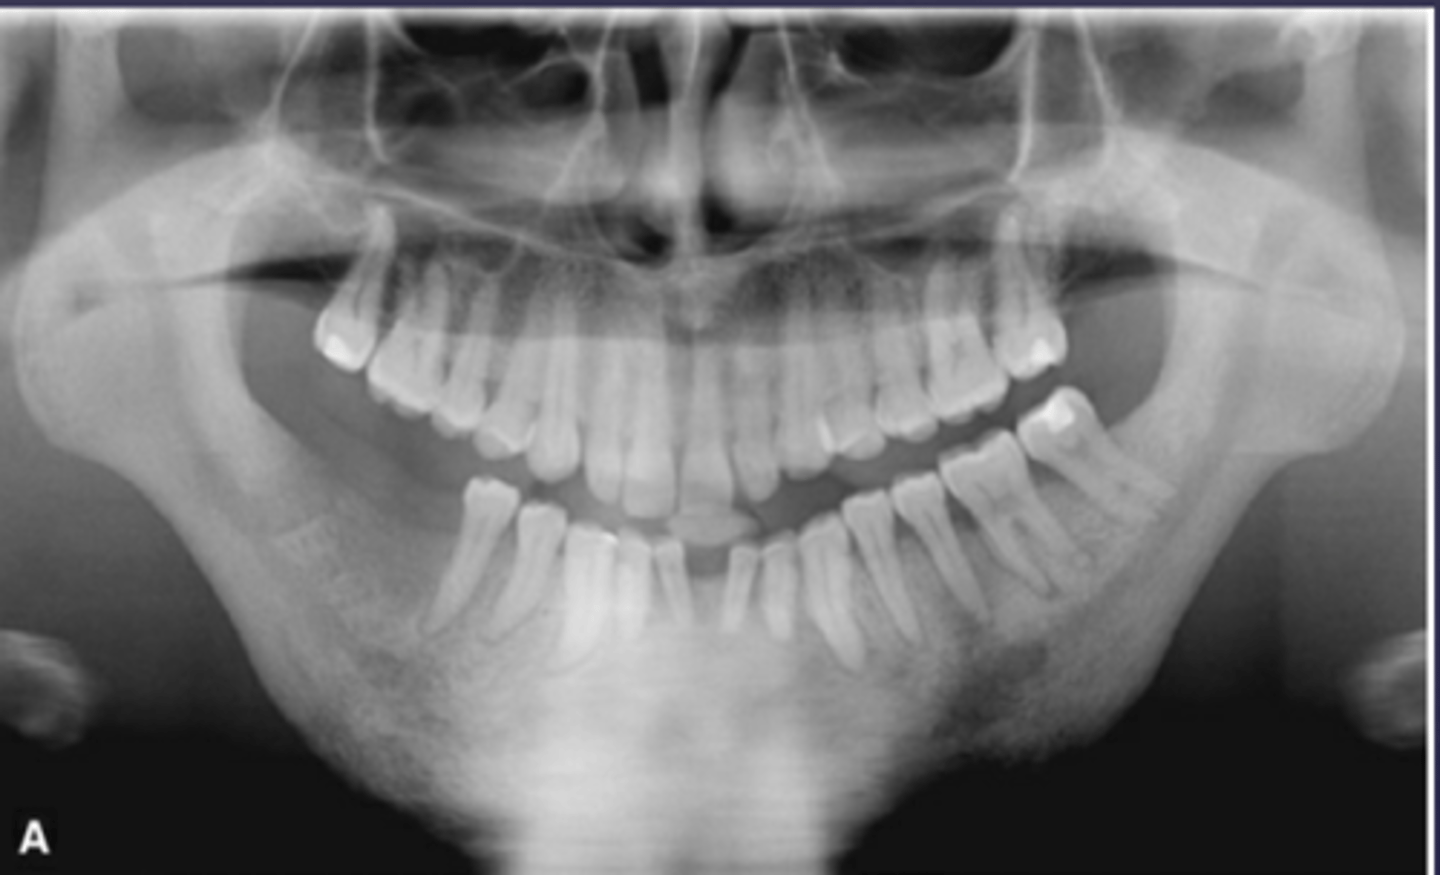

What type of osteomyelitis?

- Sclerotic appearance of involved bone

- Subperiosteal bone deposition

- Slight jaw enlargement

- Involves large segment of jaw

diffuse sclerosing osteomyelitis (chronic osteomyelitis)

What is the differential diagnosis of the left angle-ramus of mandible?